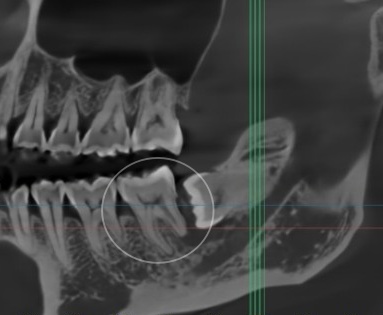

민락 치과 에서 표시한 부위를 보면

치아가 잇몸 안쪽으로 매복되어 있습니다.

이처럼 머리가 앞쪽 어금니를 향해

누운 상태의 ‘수평 매복 사랑니’는

단순히 자리를 차지하고 있는 것이 아니라

주변 치아와 잇몸 건강에 영향을 미치는

잠재적 위험 요소가 됩니다.

특히 어금니 사이에는

좁고 깊은 공간이 형성되면서

음식 찌꺼기가 쉽게 끼는 반면에

칫솔질로 청소하기 어렵고

거울로는 정확하게 확인할 수 없어

위생 관리의 사각지대가 될 수 있습니다.

치아 곳곳에는 치석이 붙어 있고

치은 연하에도 치석이 부착된 것으로 봐서

치주염을 짐작해 볼 수 있는 환경이며,

실제로 CT 사진에서도

검게 보이는 영역이 관찰됩니다.

이는 방사선이 많이 통과되었다는 뜻으로

염증 반응 및 골소실을 의미합니다.

민락 치과 에서 확인한

제일 큰 문제는 염증의 범위입니다.

앞쪽 어금니에 확산된 모습으로,

원심 뿌리의 골소실이 큽니다.